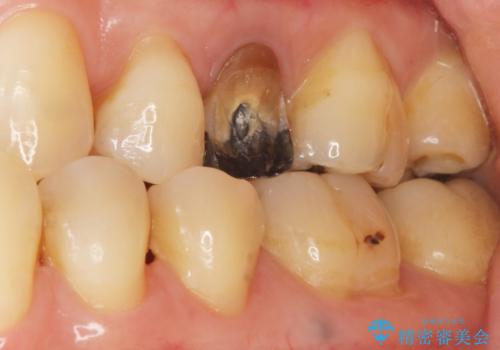

神経が死んで変色した歯 根管治療とオールセラミッククラウン